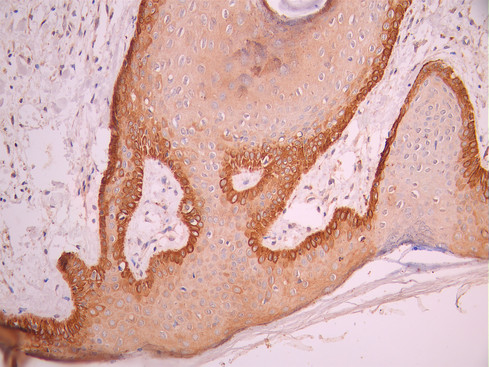

• IHC image of CSB-RA049199A0HU diluted at 1:100 and staining in paraffin-embedded human skin tissue performed on a Leica BondTM system. After dewaxing and hydration, antigen retrieval was mediated by high pressure in a citrate buffer (pH 6.0). Section was blocked with 10% normal goat serum 30min at RT. Then primary antibody (1% BSA) was incubated at 4°C overnight. The primary is detected by a Goat anti-rabbit polymer IgG labeled by HRP and visualized using 0.05% DAB.